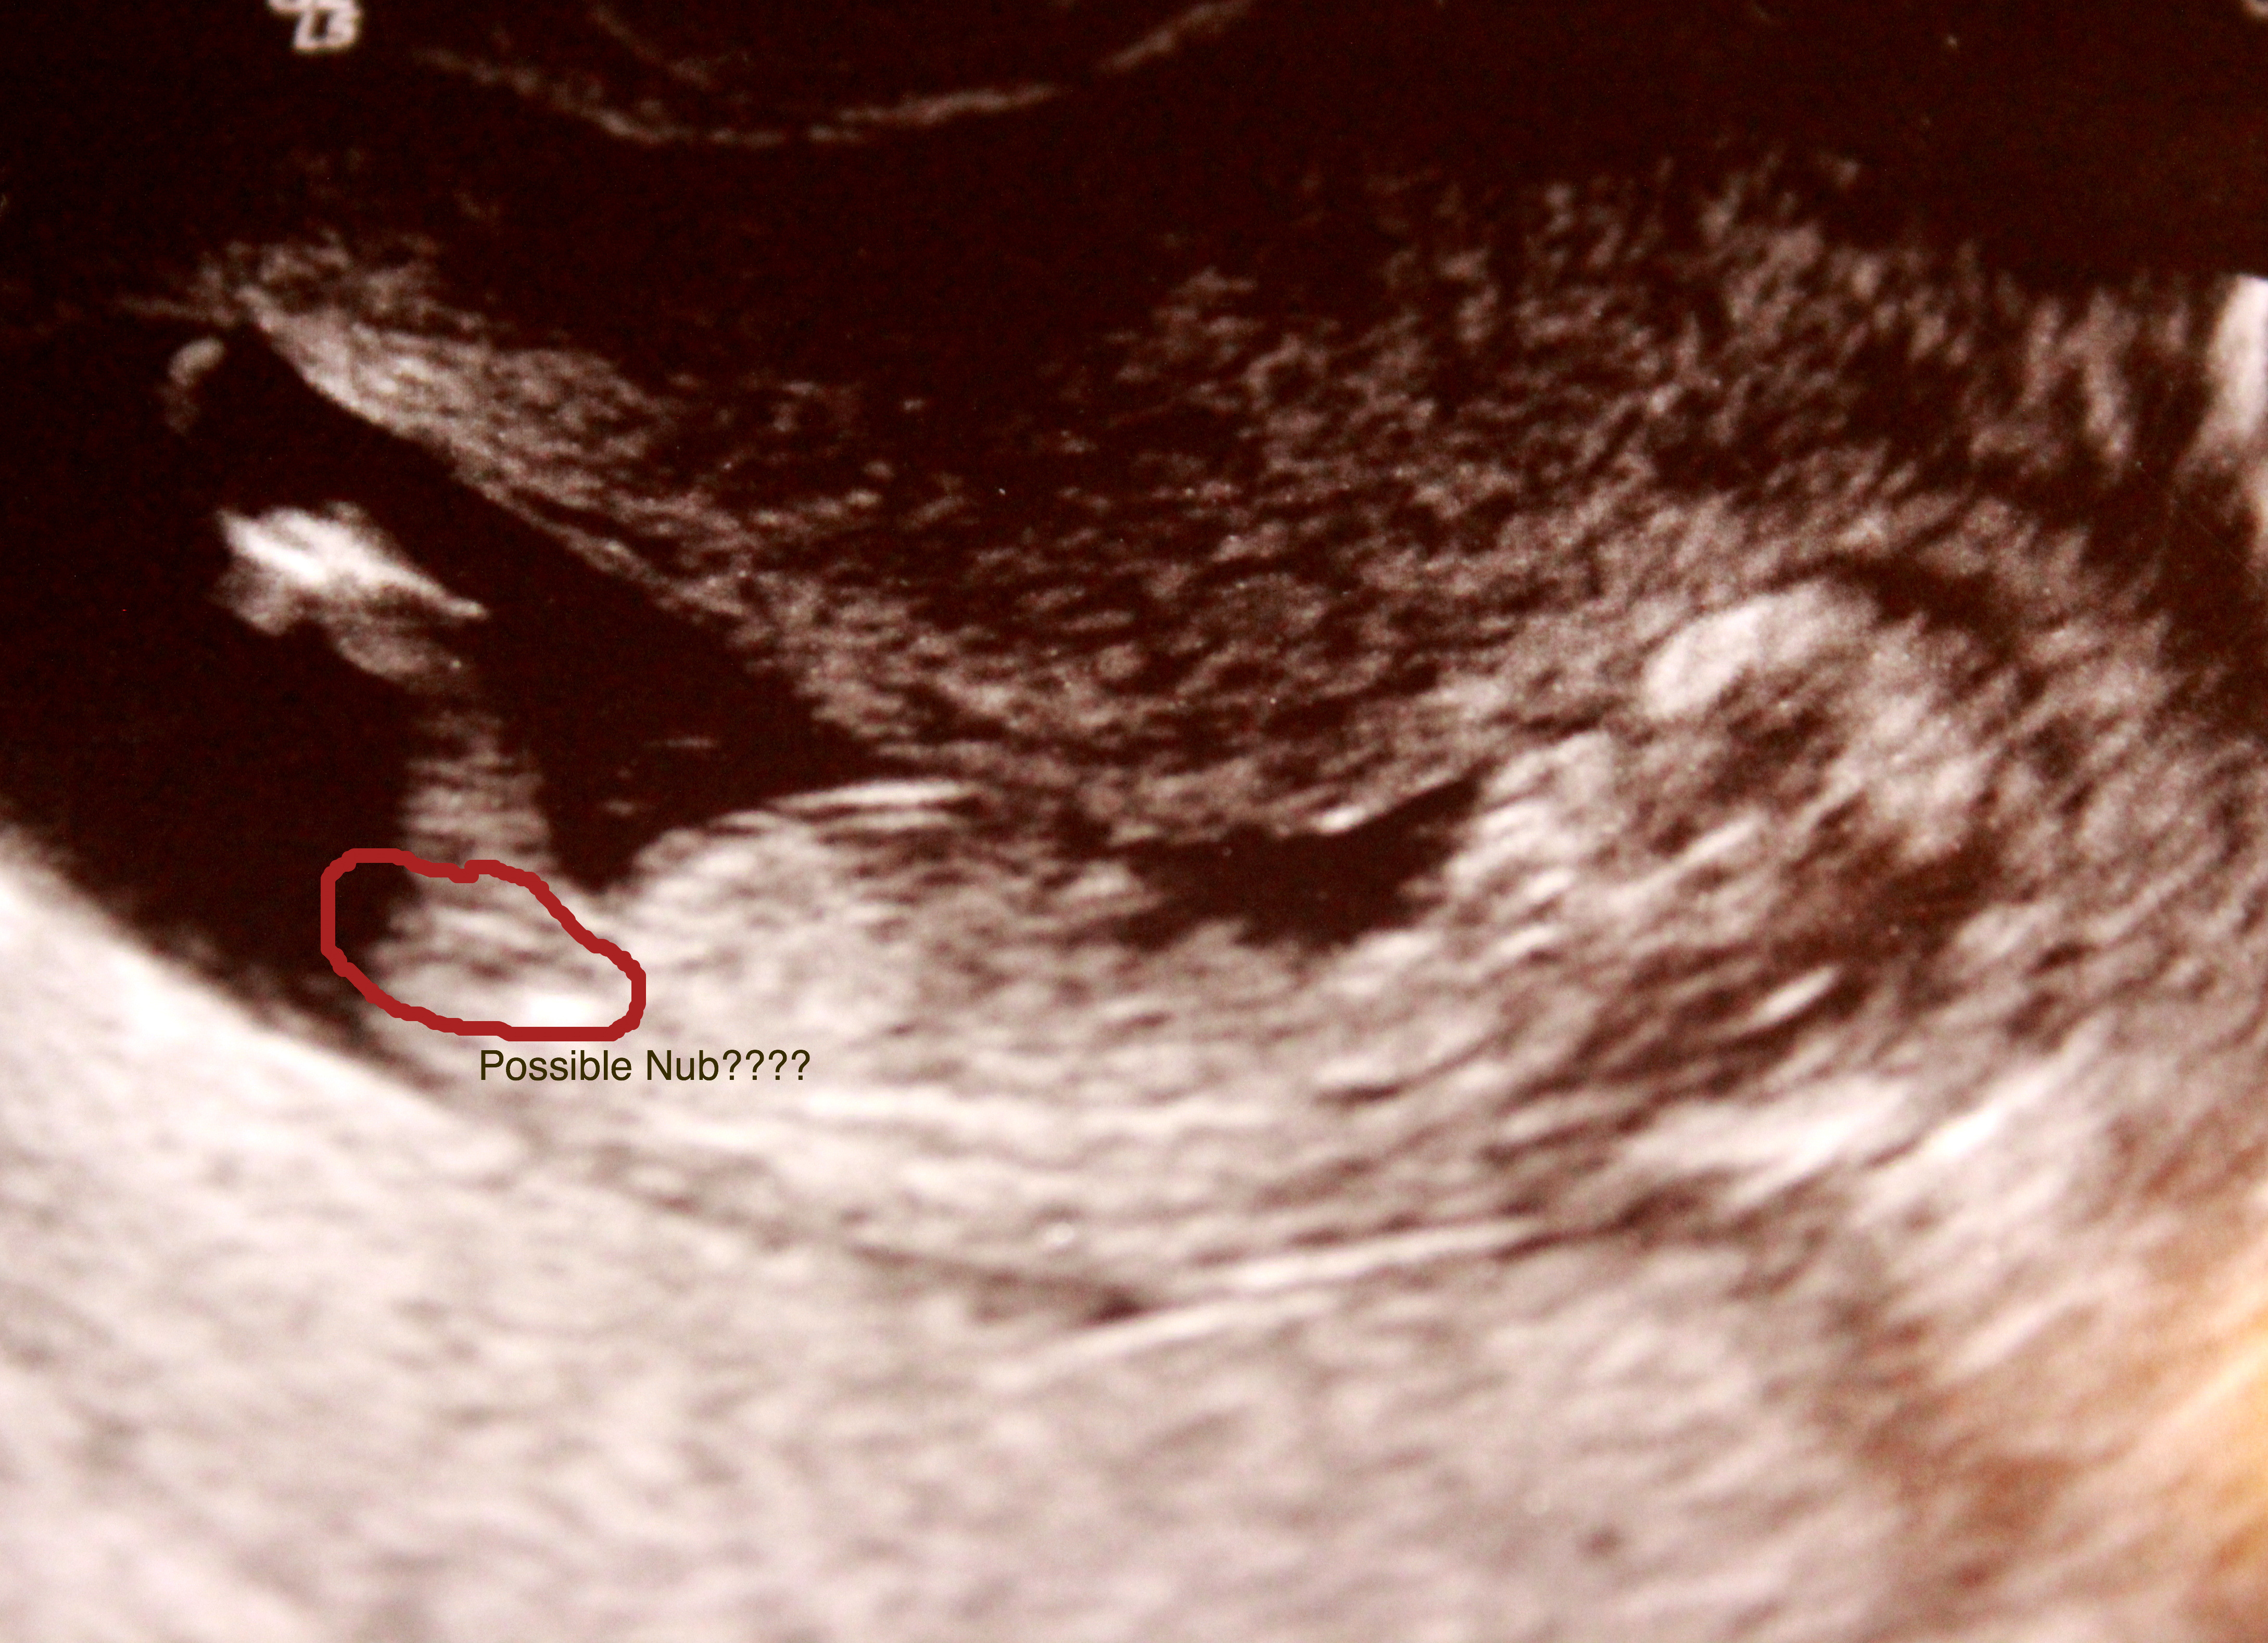

i think youve drawn over it thorz. can you post pic without circle:agree:

Attachment 9896

I think it does look like a nub. It's definitely flat too!! My fingers are crossed for you!

50/50 for me!! I am leaning girl slight but I don't think all the nub is in view!

I dunno... maybe. Im on the fence here. I think previous poster is right, it looks like a partial nub to me?

However I am leaning girl here!